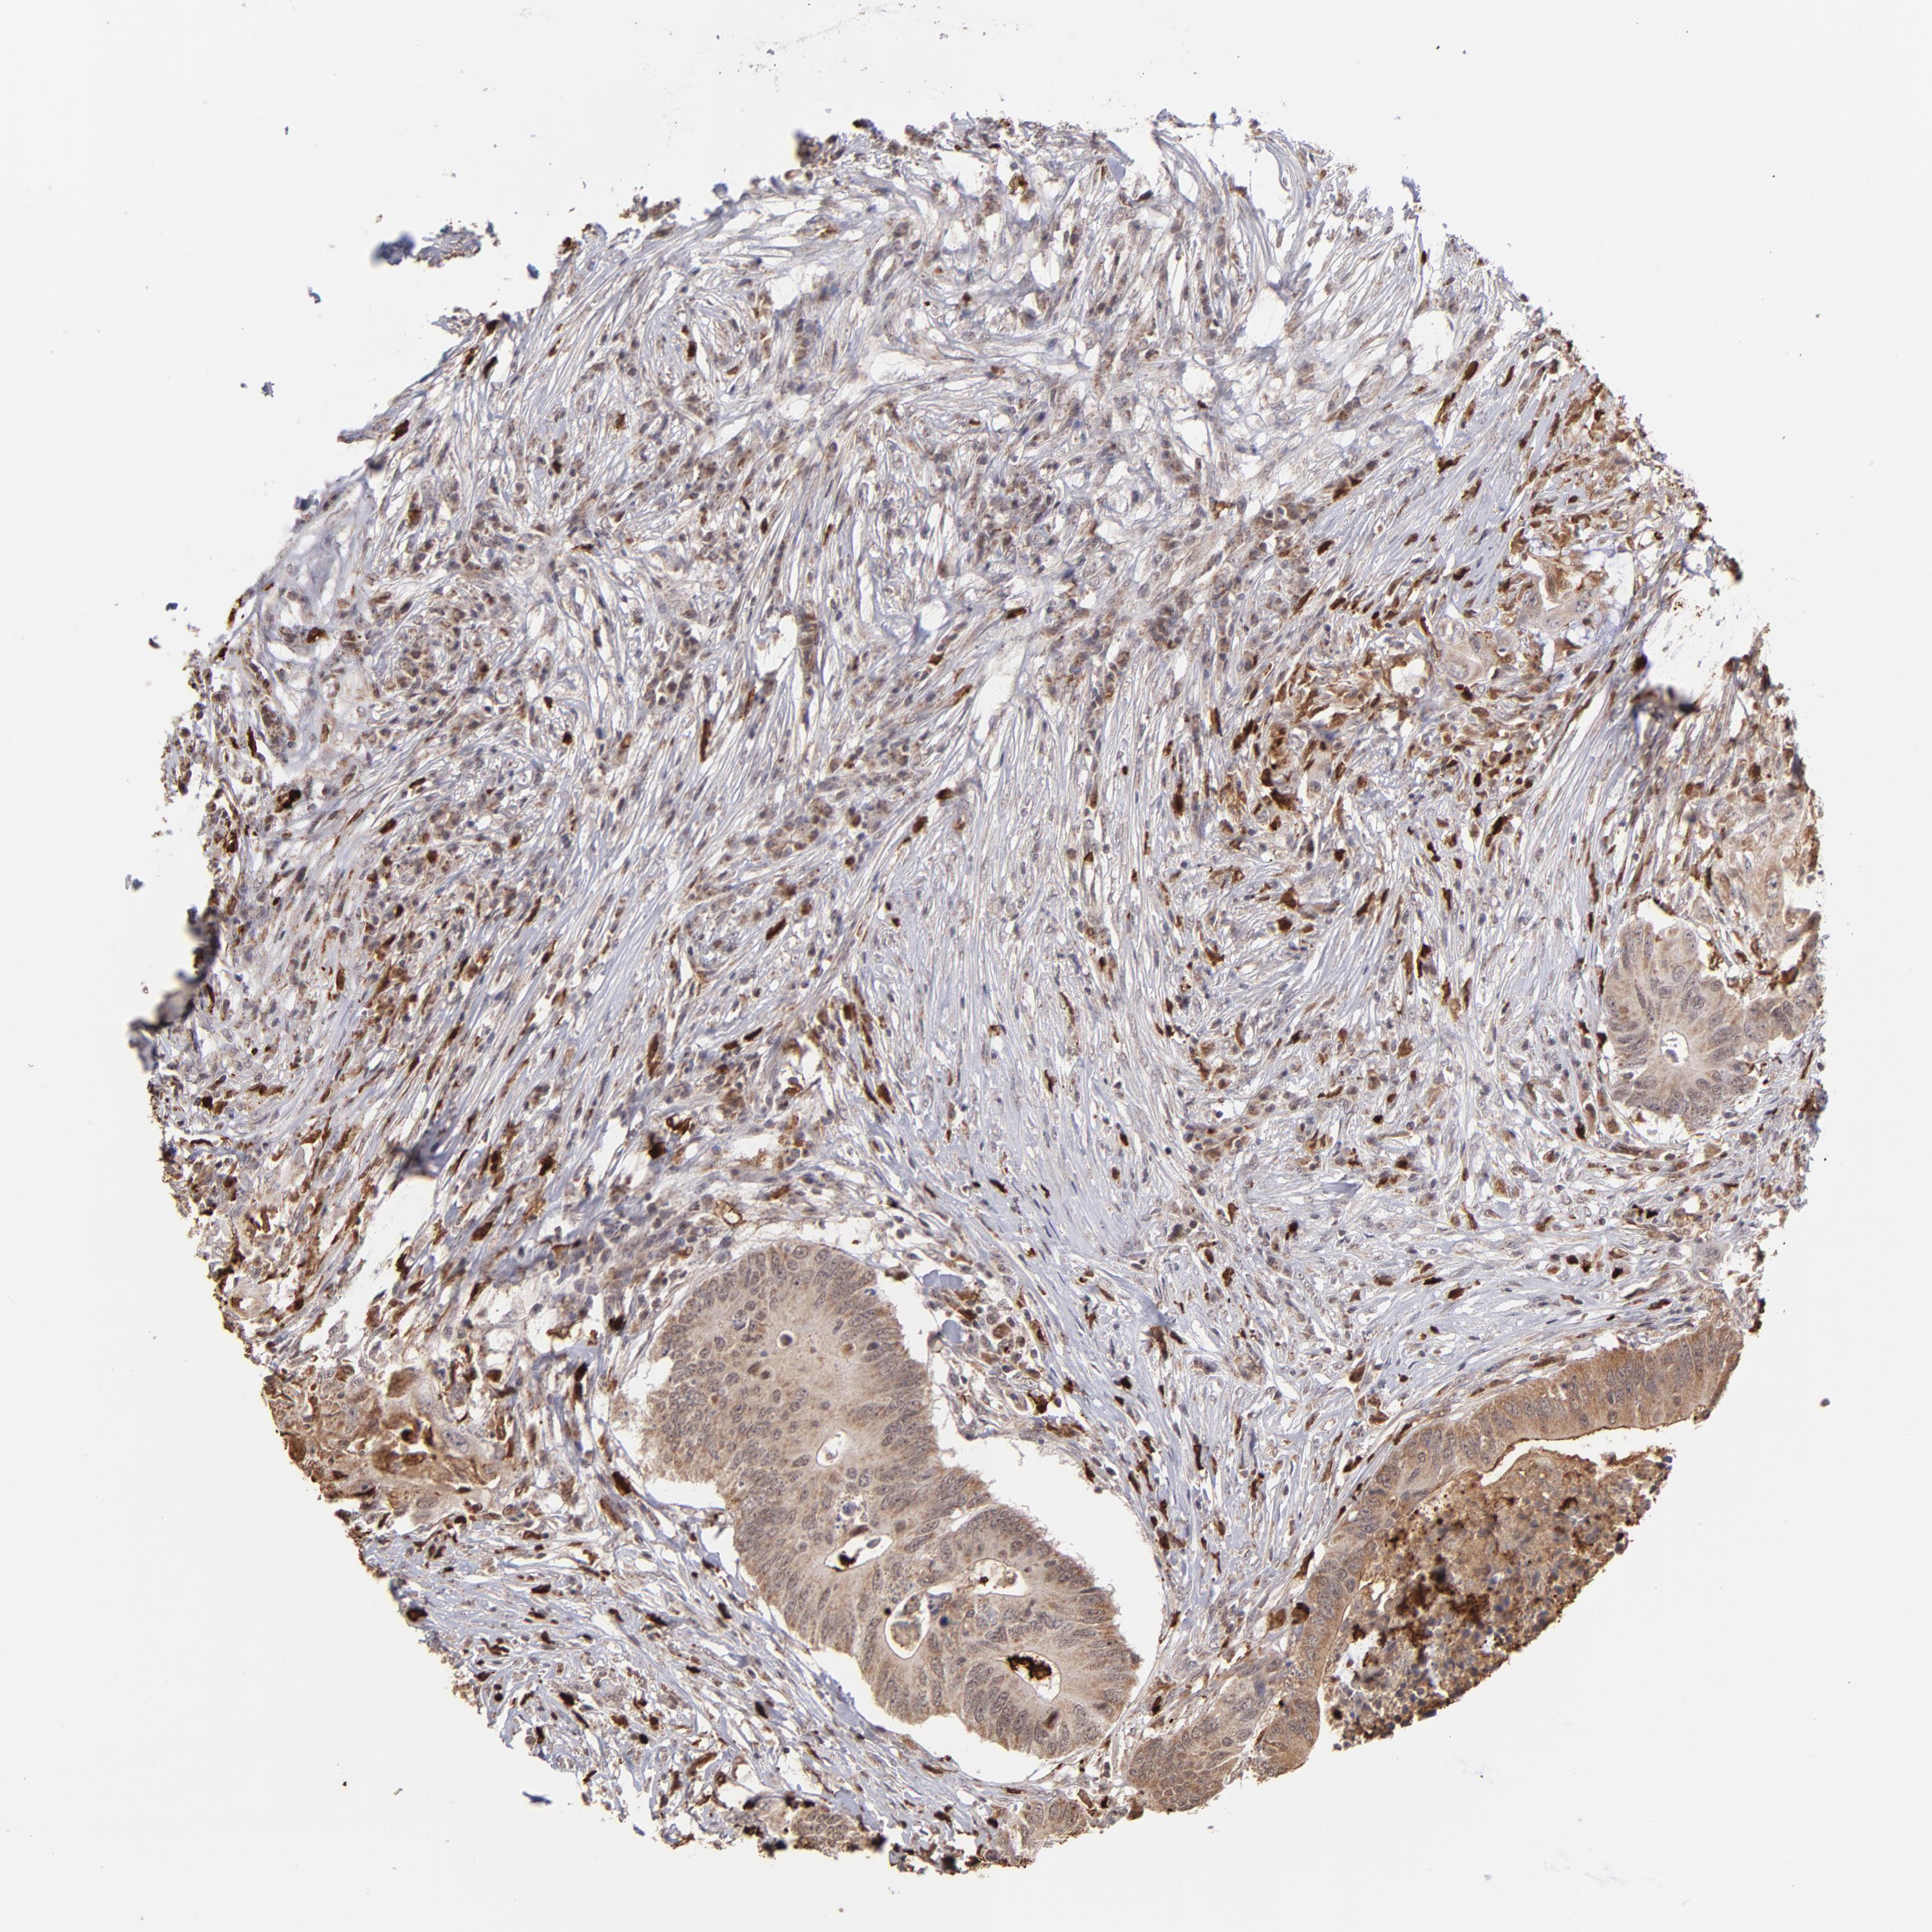

CANCER COLORECTAL CANCER Show tissue menu

Colorectal cancer

Human cancer

Colon adenocarcinoma